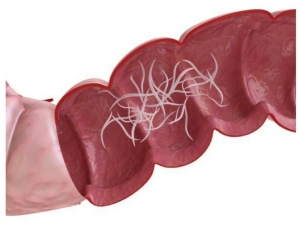

Li si conosce poco, eppure non sono così rari. Parliamo degli ossiuri, chiamati più comunemente parassiti intestinali, piccoli esseri che colonizzano il tratto intestinale causando fastidi e pruriti. Ma come si riconoscono? E come si combattono?

Gli ossiuri, i parassiti intestinali che colpiscono adulti e bambini e i rimedi naturali: come riconoscere se si è affetti da questa infestazione intestinale e come curarsi in maniera naturale